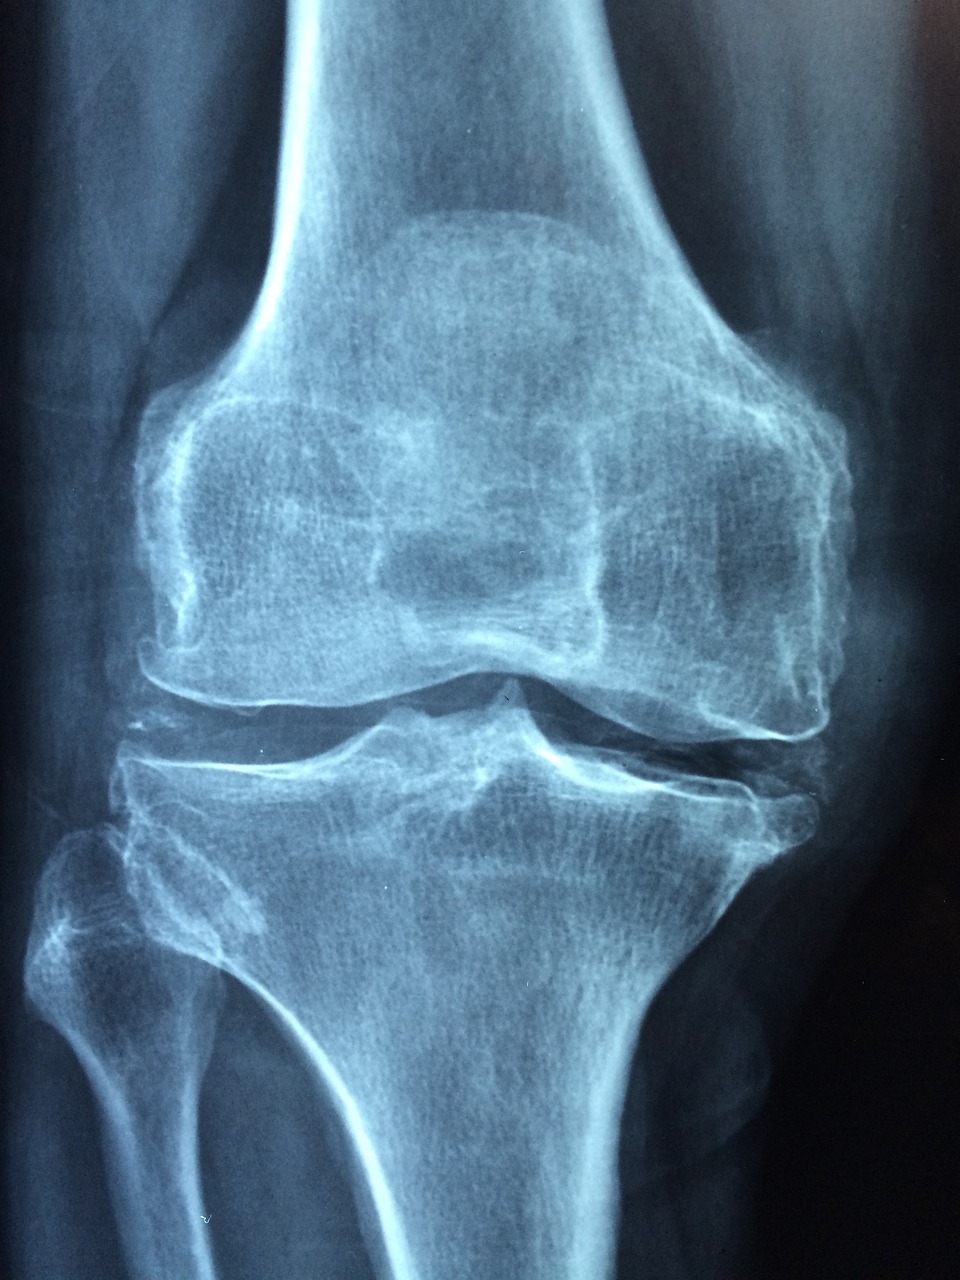

골다공증 예방을 위해 가장 중요한 영양소는 칼슘과 비타민 D입니다. 칼슘은 뼈의 주요 구성 성분으로, 충분한 섭취가 이루어지지 않으면 뼈의 밀도가 감소하고 골절 위험이 높아집니다. 비타민 D는 칼슘의 흡수를 돕는 역할을 하며, 부족할 경우 칼슘이 체내에서 제대로 활용되지 못하고 뼈 건강이 악화될 수 있습니다. 고령자는 칼슘 흡수율이 낮아지므로 일반 성인보다 더 많은 양을 섭취하는 것이 권장됩니다. 칼슘이 풍부한 식품으로는 우유, 치즈, 요구르트 등의 유제품, 뼈째 먹는 생선(멸치, 연어), 두부, 시금치, 브로콜리 등이 있습니다. 또한, 비타민 D는 햇볕을 통해 체내에서 합성되지만, 고령자는 피부의 비타민 D 합성 능력이 저하되므로 연어, 참치, 달걀노른자, 비타민 D 강화 유제품 등의 식품을 통해 보충해야 합니다. 필요할 경우 의사의 상담을 받아 비타민 D 보충제를 섭취하는 것도 좋은 방법입니다.

영양 섭취뿐만 아니라 건강한 생활 습관과 적절한 운동도 골다공증 예방에 필수적입니다. 특히 체중 부하 운동(걷기, 계단 오르기, 가벼운 근력 운동)은 골밀도를 유지하고 뼈를 튼튼하게 하는 데 도움을 줍니다. 규칙적인 운동은 근력을 강화하여 골절 위험을 줄이고, 균형 감각을 향상시켜 낙상을 예방하는 효과도 있습니다. 햇볕을 충분히 쬐어 비타민 D 합성을 촉진하는 것도 중요합니다. 또한, 충분한 수면과 스트레스 관리는 뼈 건강을 유지하는 데 도움이 되므로 규칙적인 생활 습관을 실천하는 것이 필요합니다. 정기적인 골밀도 검사를 통해 자신의 뼈 건강 상태를 확인하고, 필요할 경우 전문가의 상담을 받아 적절한 영양 및 생활 습관을 조정하는 것도 좋은 방법입니다. 균형 잡힌 영양 섭취와 건강한 생활 습관을 실천하면 골다공증 예방뿐만 아니라 전반적인 건강을 유지하는 데도 큰 도움이 됩니다.